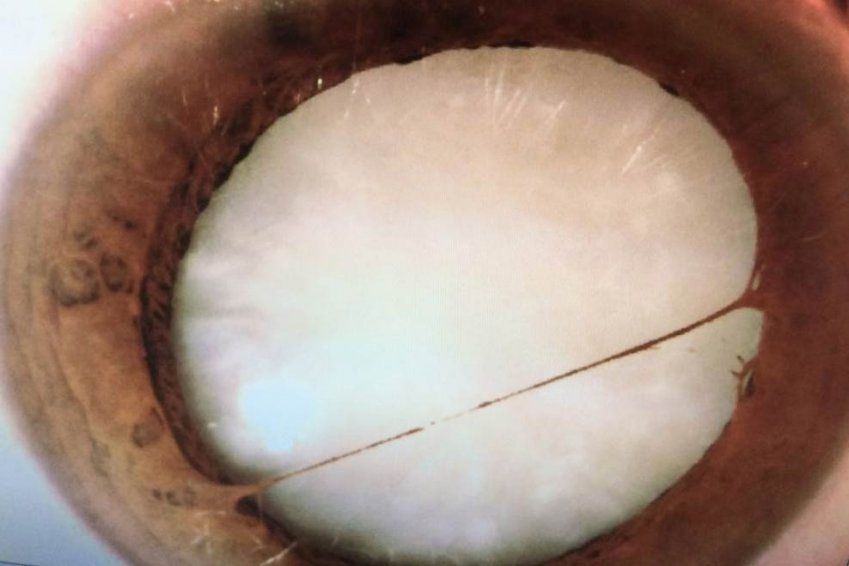

La catarata es la pérdida de transparencia u opacificación del cristalino. El cristalino es una lente natural, que en las personas jóvenes tiene una perfecta elasticidad y una transparencia total. Los rayos de luz lo atraviesan para formar las imágenes en la retina.

El paso del tiempo provoca que el centro del cristalino se endurezca y disminuya así la capacidad para enfocar objetos. Asimismo el tiempo causa la opacificación y la pérdida de la transparencia inicial.